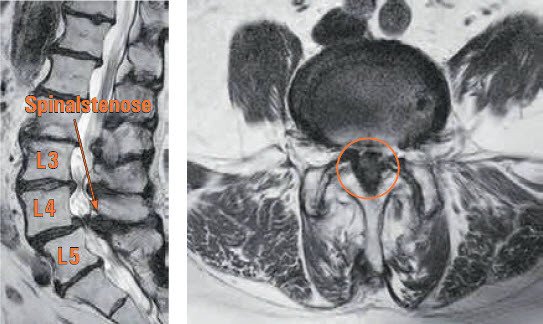

Abb. 1 – 2 (präoperativ) und Abb. 3 – 4 (postoperativ) zeigen MRI-Bilder der Lendenwirbelsäule. Zwischen dem 4. und 5. Lendenwirbel (L4 / L5) ist ein Wirbelgleiten und eine hochgradige Spinalstenose (Pfeil) ersichtlich. Die Einengung auf Höhe L3 / L4 ist weniger ausgeprägt.

Abb. 3 – 4 zeigen MRI-Bilder nach der Dekompressionsoperation. Zwischen dem 4. und 5. Lendenwirbel (L4 / L5) ist weiterhin ein Wirbelgleiten ersichtlich, aber die Spinalstenose ist nicht mehr vorhanden (Pfeil). Durch die Operation konnte die Einengung auch auf Höhe L3 / L4 beseitigt werden.